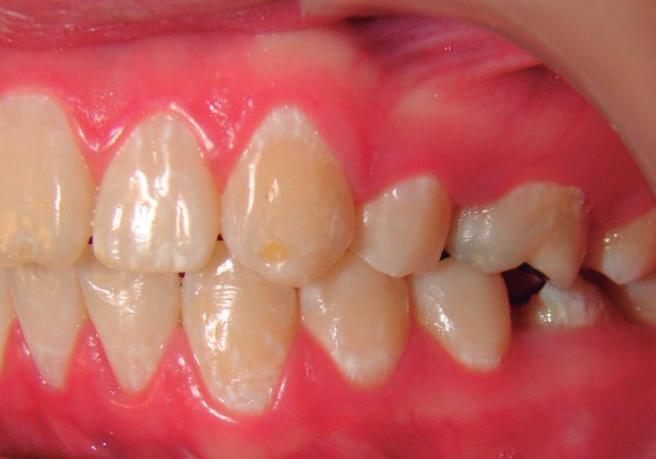

Este manual proporciona información completa y actualizada para profesionales de la odontología acerca de la amelogénesis imperfecta, una enfermedad huérfana que se caracteriza por desórdenes hereditarios que afectan la estructura del esmalte en su calidad y cantidad. Esta patología muchas veces se subdiagnostica en la práctica general, por lo que este manual suministrará una guía que permitirá un diagnóstico certero; además, brindará una clara y comprensible explicación a otros profesionales de la salud, como médicos y nutricionistas, que podrían interactuar con pacientes afectados por esta enfermedad, ya que esta entidad se ha asociado también a factores nutricionales y a enfermedades sistémicas.

A pesar de los recientes avances en la identificación de los defectos moleculares responsables de la aparición de la amelogénesis imperfecta, existe poca información sobre el fenotipo y el genotipo de este

grupo de desórdenes, lo que dificulta el diagnóstico de algunos subtipos clínicos y, por lo tanto, la determinación del programa terapéutico. Describir las características dentales y craneofaciales, así como otras enfermedades asociadas que pueden estar relacionadas con pacientes que padecen amelogénesis imperfecta, proporciona elementos para una adecuada planeación de su tratamiento. La intervención de varios profesionales para remediar los múltiples y severos problemas funcionales y estéticos presentes en esta enfermedad se hace necesaria, así como conocer su etiología genética, con el fin de brindar al paciente una atención integral.